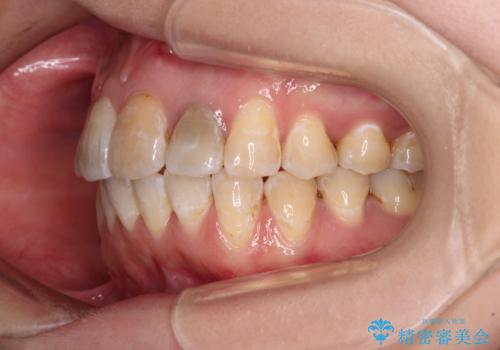

- 重なった前歯を邪魔に感じ、汚れも溜まりやすいことを気にして来院された患者様です。

右上前から2番目の歯が内側に転位しているため、上顎の正中は右にずれていました。

内側に転位していた歯はきれいに歯列に収まり、清掃性が著しく改善しました。

元々神経の失活してしまっている前歯2本は変色が目立つようになってきたため、今後セラミッククラウンによる補綴治療を行う予定です。